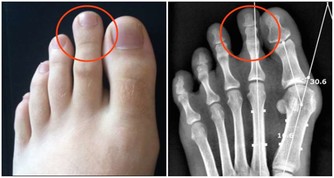

在圍餐中很少使用公筷,同桌進餐中有人感染幽門螺旋桿菌,就有可能通過共用碗筷、唾液導致交叉感染。慢性胃炎、胃十二指腸潰瘍甚至胃癌,都可能與幽門螺桿菌感染有關。